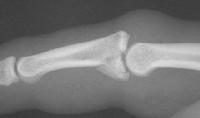

Clinical Example: PIP fracture dislocation treated with force couple splint

Proximal interphalangeal joint fracture dislocation is a common and difficult injury. There are many possible treatment techniques. Here, the force couple splint method was used.